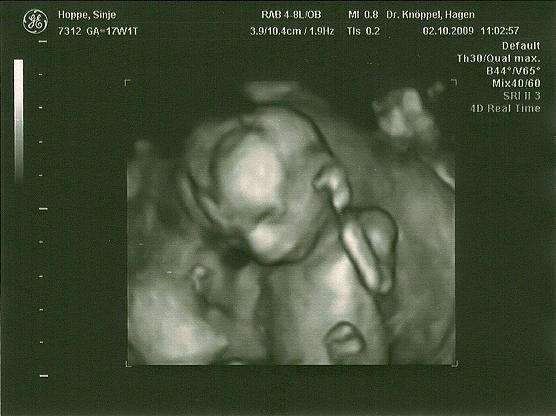

Hallo ich bin wieder zurück von der VU. War alles super Ausgangsgewicht + 1 kg, Blutdruck 110/70 und Urin und Abstrich auch super. Der US war auch toll haben sigar schon nen 3D Bild gemacht... Und der Krümel liegt in BEL. Naja aber zeigen wollte er/sie sich nicht :( grml. Mein Mann nd ich haben doch ne Wette laufen. Er hat gesucht und gesucht aber es hatte immer schön die Beine, Nabelschnur und Füße davor.... Da konnteman nix machen wirhaben 10 min. gesucht.... Mensch naja wieder 4 Wochen warten:(

is das schän das 3D bild so genau :)

Ich finde 3D-Bilder irgendwie immer etwas gruselig.... aber toll sind beide, süßes Gesichtchen! Was ich aber nicht verstehe - in exakt dieser Haltung lag mein Zwerg vor zwei Tagen auch und der Arzt hat dann einfach nur die Tiefenschärfe etwas verändert, so dass wir zwischen den Beinen gelandet sind und beste Sicht hatten ;-) Man muss doch nicht zwingend von vorne draufgucken *wunder*? Hängt aber vielleicht vom US-Gerät ab? Hm....

Sehr schöne Bilder Ich finde ja das Kleine sieht aus wie ein Junge Aber wer weiß

Mensch, schade, dass es sich nicht geoutet hat. Finde aber auch, dass es nach Junge aussieht!!

Ach wie süüüüüüüüüüüüüss die Bilder echt da freu ich mich schon weider auf meinen Termin... noch 12 Tage Echt das erste Bild ist wahnsinn da sieht man schon wie hübsch das Babylein ist grins.. GLG Jessi